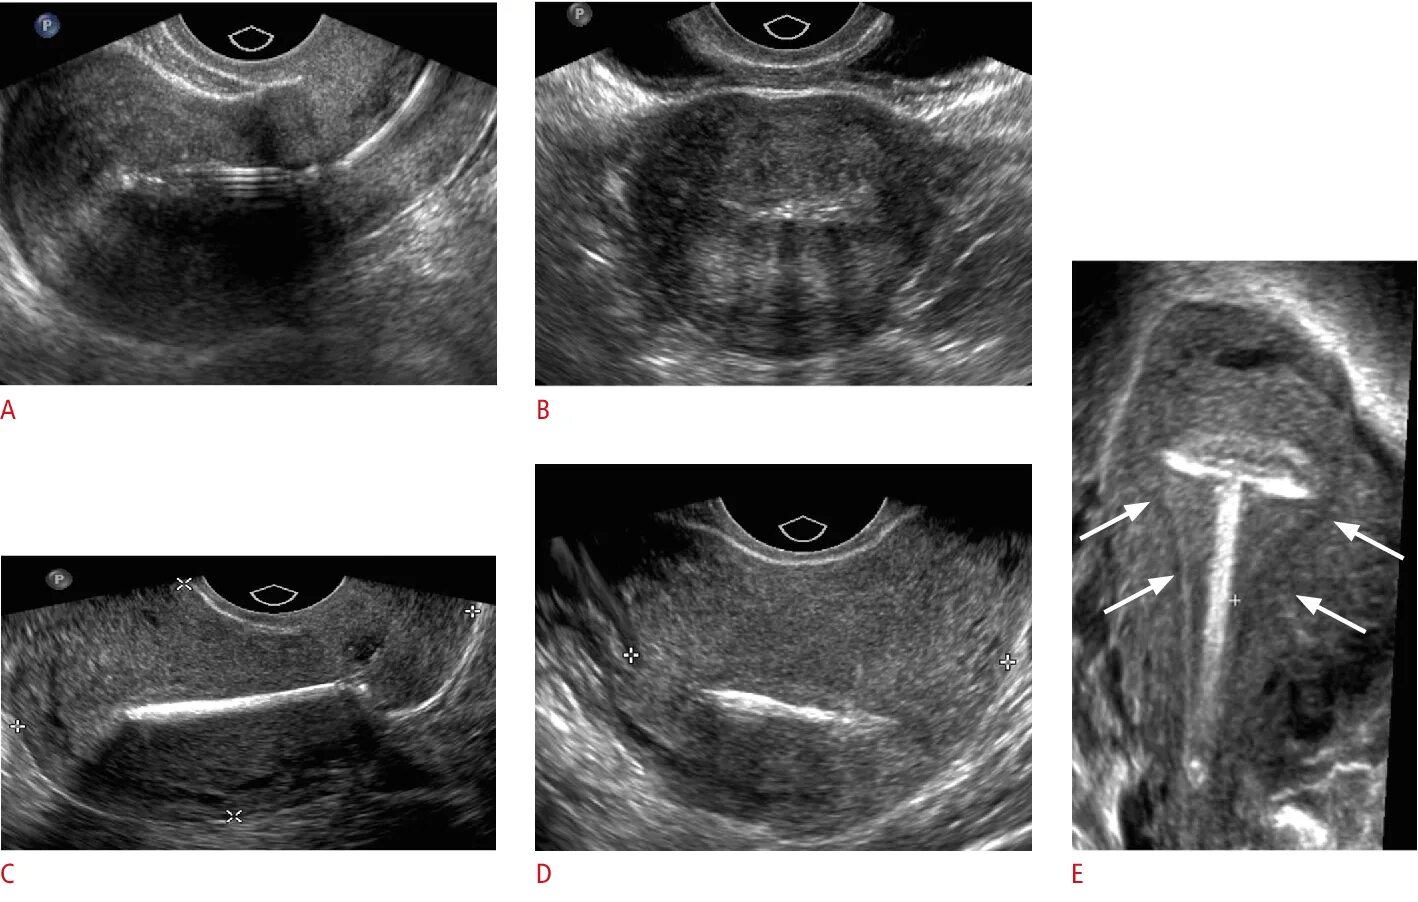

Зев т образный